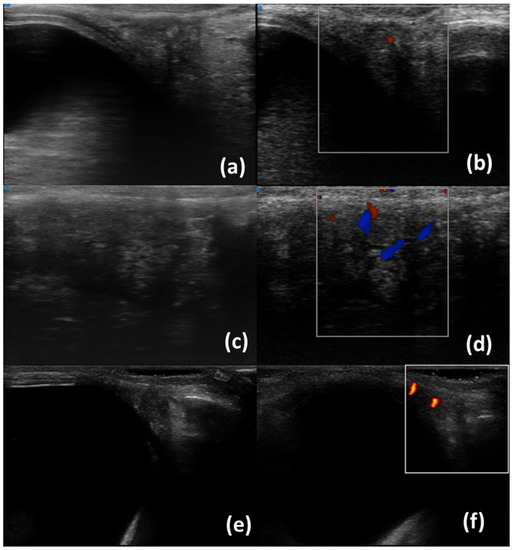

- Aringhieri, G.; Izzetti, R.; Vitali, S.; Ferro, F.; Gabriele, M.; Baldini, C.; Caramella, D. Ultra-high frequency ultrasound (UHFUS) applications in Sjogren syndrome: Narrative review and current concepts. Gland. Surg. 2020, 9, 2248–2259. [Google Scholar] [CrossRef] [PubMed]

- Ferro, F.; Izzetti, R.; Vitali, S.; Aringhieri, G.; Fonzetti, S.; Donati, V.; Dini, V.; Mosca, M.; Gabriele, M.; Caramella, D.; et al. Ultra-high frequency ultrasonography of labial glands is a highly sensitive tool for the diagnosis of Sjögren’s syndrome: A preliminary study. Clin. Exp. Rheumatol. 2020, 38 (Suppl. S126), 210–215. [Google Scholar]

- Fulvio, G.; Ferro, F.; Izzetti, R.; Governato, G.; Fonzetti, S.; La Rocca, G.; García, I.C.N.; Donati, V.; Mosca, M.; Baldini, C. POS1461 advantages of doppler in labial salivary gland ultra-high frequency ultrasound: Correlations with histological inflammation, pSS diagnosis, disease activity, and prognosis. Ann. Rheum. Dis. 2023, 82 (Suppl. S1), 1085. [Google Scholar] [CrossRef]